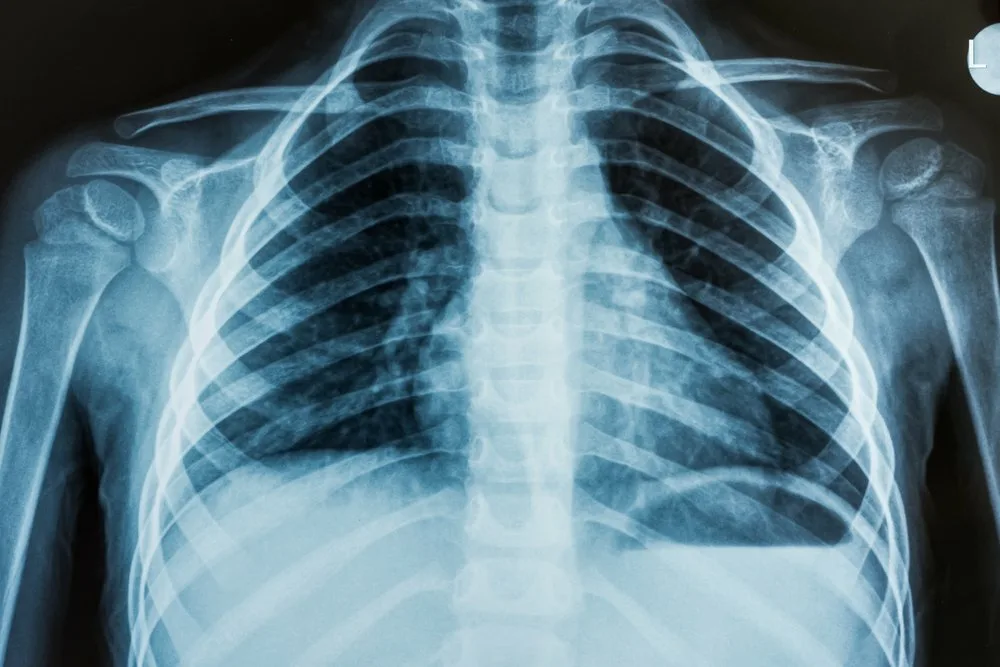

• Рентген; позволит оценить состояние костей и органов дыхания;